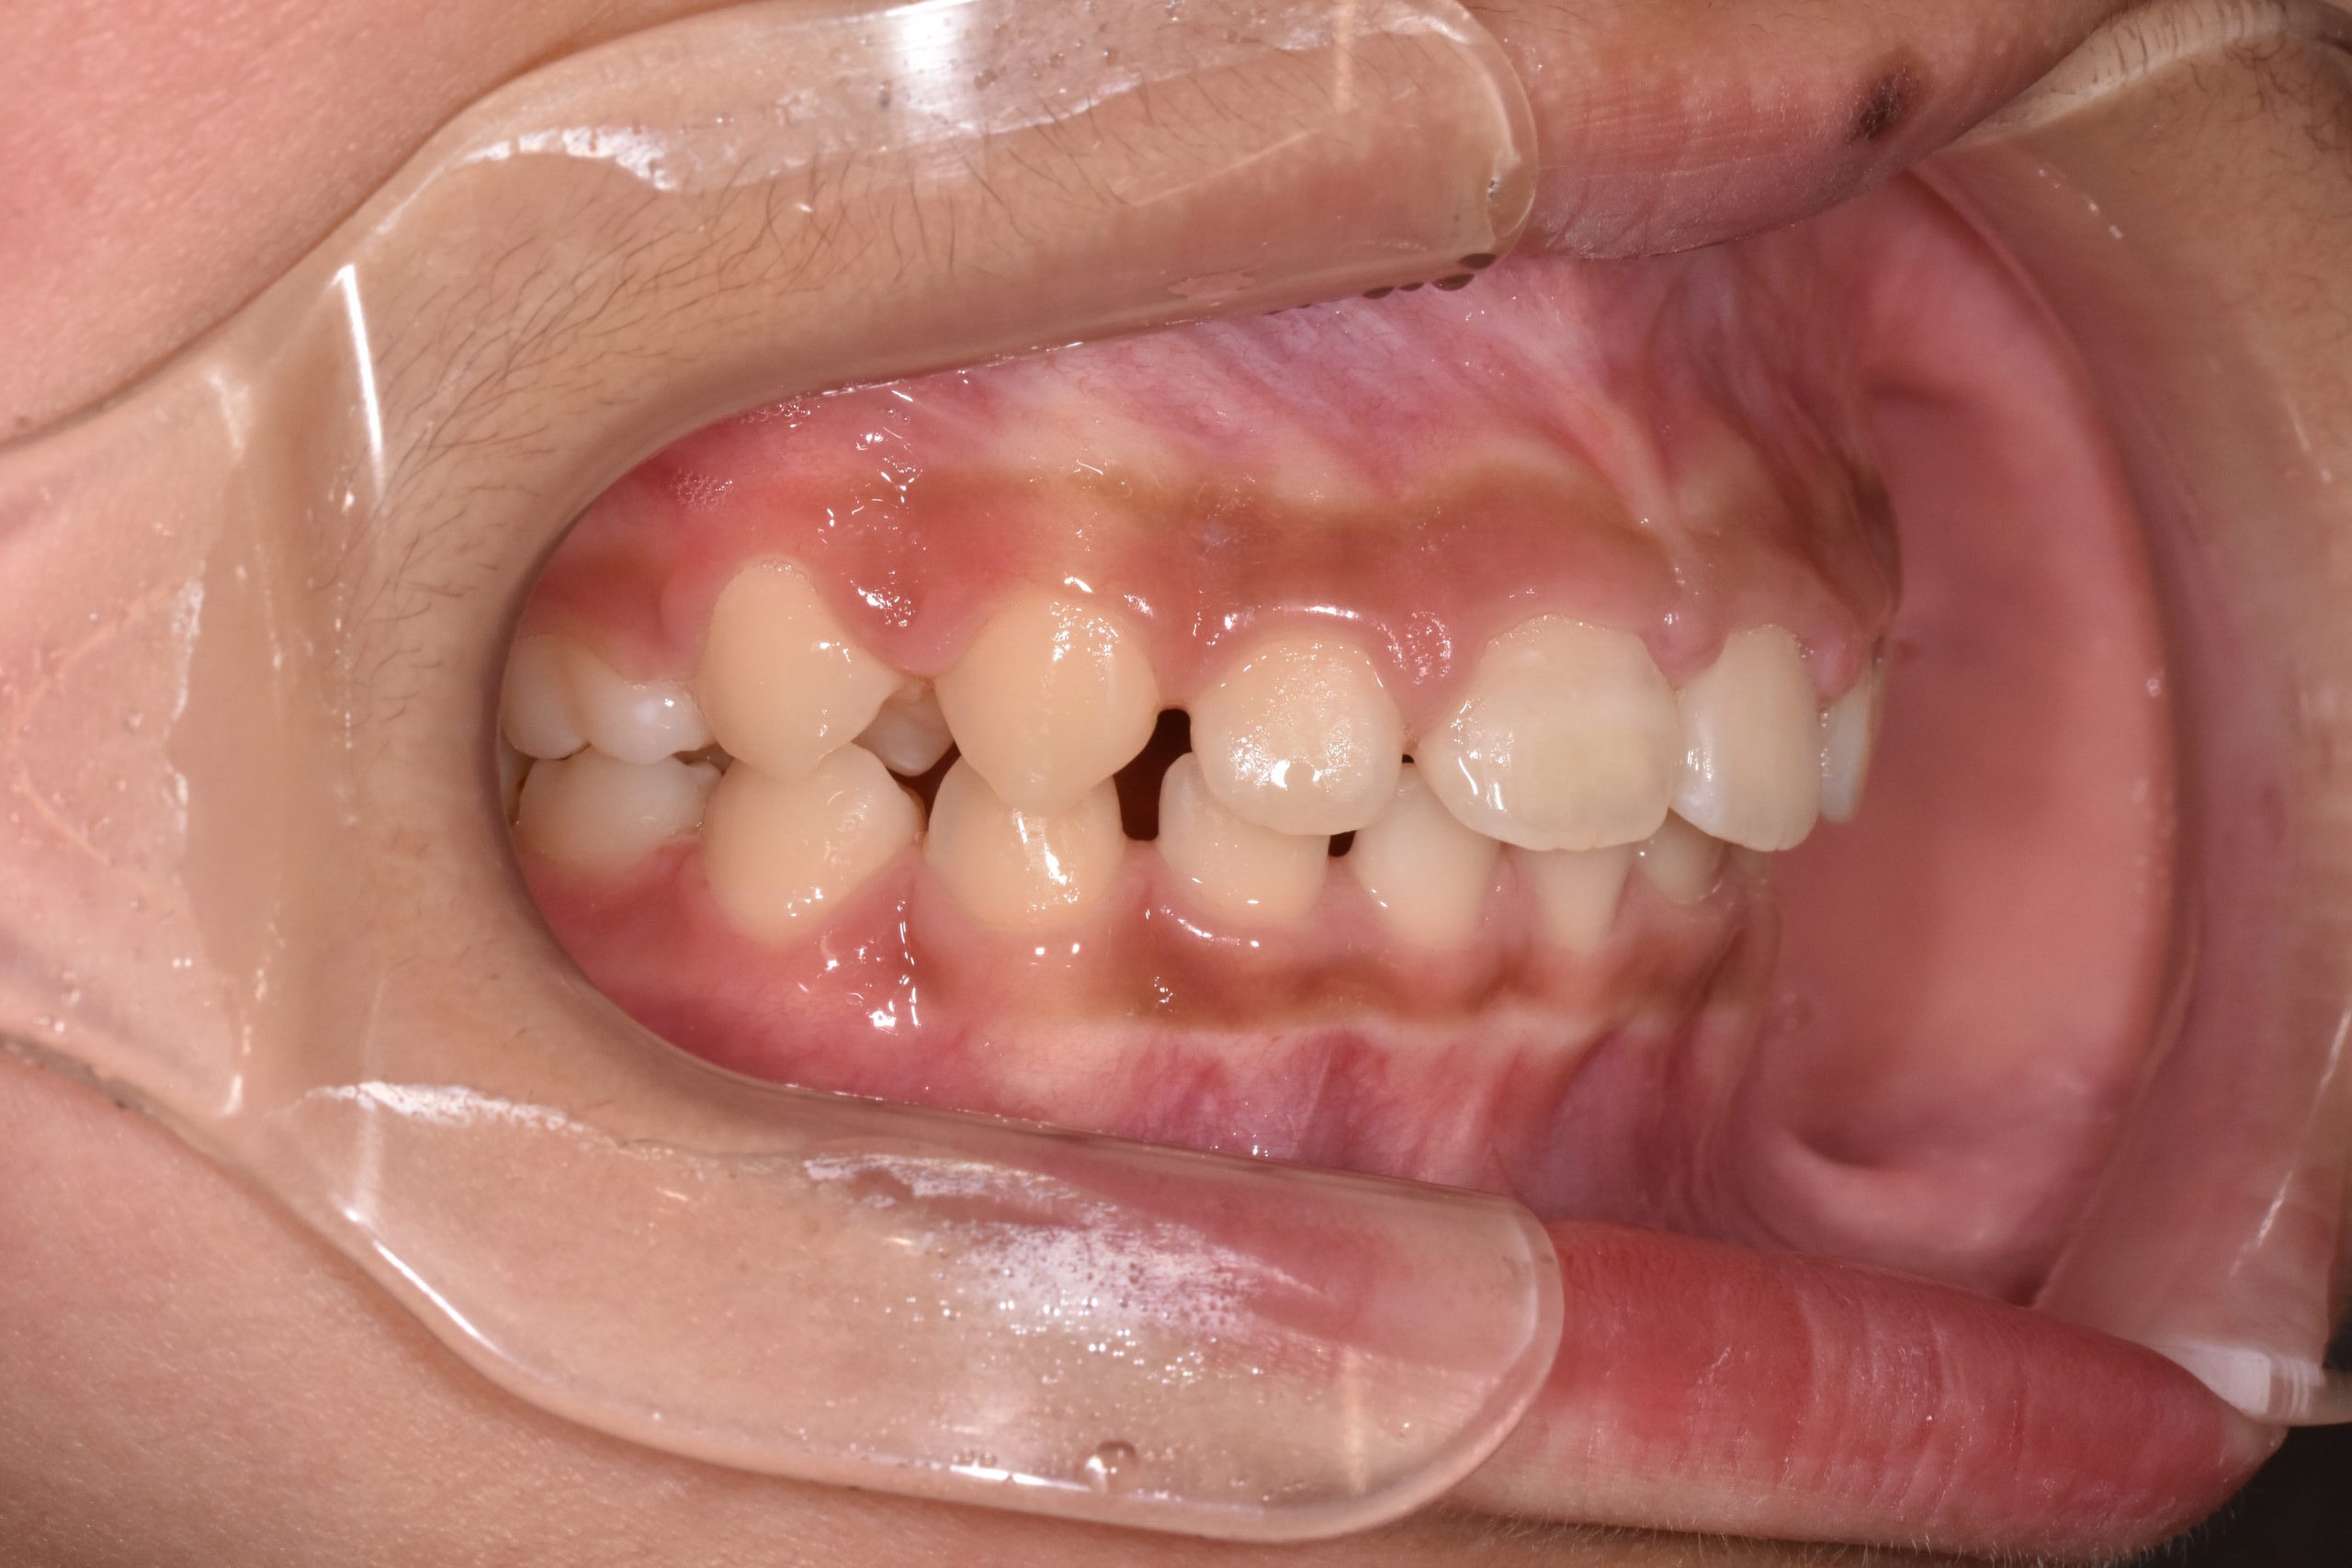

治療後

成長を利用した1期治療にて、マウスピース型装置や矯正装置を用い、歯並びと口元のバランスの改善を行いました

・成長期を活かし、口元の突出感を改善

・歯並びだけでなく、横顔(Eライン)にも配慮

・将来的な抜歯や本格矯正の負担軽減を目指した治療

・必要に応じて2期治療へ移行できるよう設計